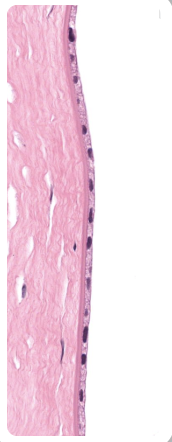

Epithelial Tissues Matching Game

Test your knowledge about epithelial tissues with this fun matching pairs game!